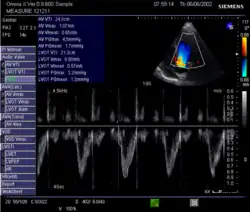

Echocardiography is a non-invasive method of quantifying cardiac output using ultrasound. Two-dimensional (2D) ultrasound and Doppler measurements are used together to calculate cardiac output. 2D measurement of the diameter (d) of the aortic annulus allows calculation of the flow cross-sectional area (CSA), which is then multiplied by the VTI of the Doppler flow profile across the aortic valve to determine the flow volume per beat (stroke volume, SV). The result is then multiplied by the heart rate (HR) to obtain cardiac output. Although used in clinical medicine, it has a wide test-retest variability.[9] It is said to require extensive training and skill, but the exact steps needed to achieve clinically adequate precision have never been disclosed. 2D measurement of the aortic valve diameter is one source of noise; others are beat-to-beat variation in stroke volume and subtle differences in probe position. An alternative that is not necessarily more reproducible is the measurement of the pulmonary valve to calculate right-sided CO. Although it is in wide general use, the technique is time-consuming and is limited by the reproducibility of its component elements. In the manner used in clinical practice, precision of SV and CO is of the order of ±20%.